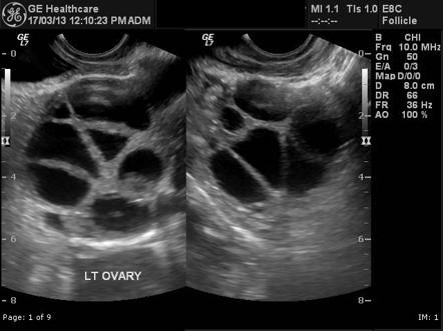

• Development of large number of follicles